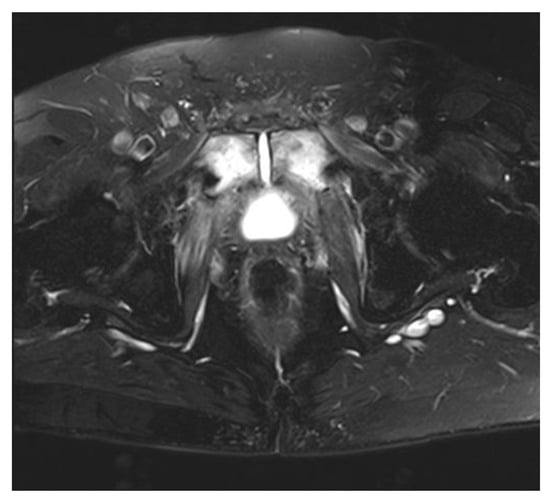

2. Pubic Osteomyelitis with Urosymphyseal Fistulae